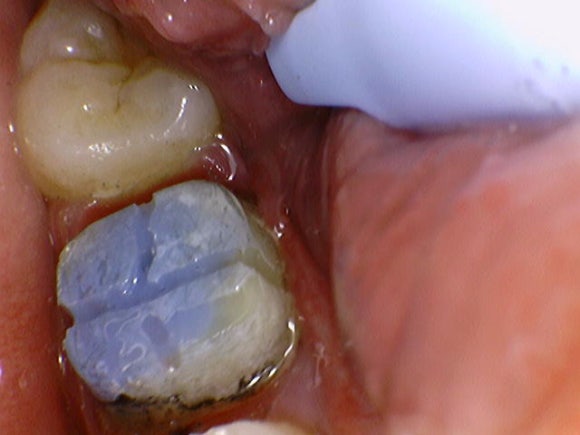

20241224

재신경치료를 위해

크라운을 벗겨냈습니다.

다행히 크라운 속으로 충치가 생기진 않았습니다.

재신경치료만 잘 된다면

다시 크라운을 씌울 수 있는 상태입니다.